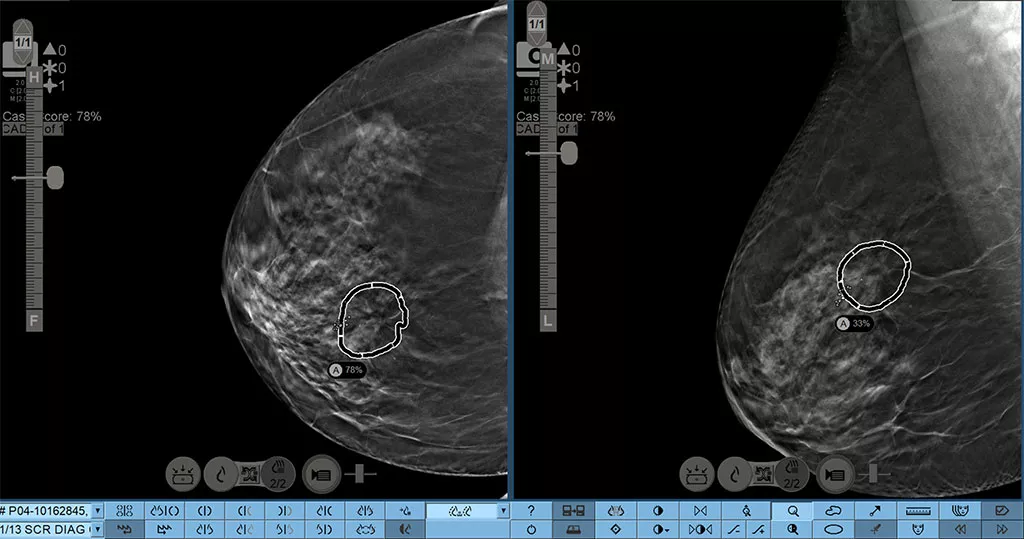

Breaking boundaries with the automated lesion correlation feature.

Hologic Genius AI Detection 2.0 solution creates automated lesion correlation markings between CC and MLO views that can be viewed in the SecurView 12.0 software*. Marks can be displayed on individual tomosynthesis slices and overlaid on 3DQuorum SmartSlices, as well as, both FFDM and synthesized 2D images. There are advanced tools to provide quick navigation to relevant correlate lesion on a specific image slice. *Check your PACS vendor for feature availability

Case Score

Case Score indicates the confidence, determined by Al, that a case contains a malignant lesion.